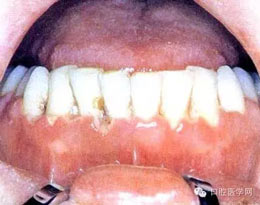

(二)毛狀白斑:為白色不能除去的病變,常開始于舌側(cè)緣,表面有皺折,呈毛狀外觀。

(五)牙周炎:為牙周軟組織喪失及不規(guī)則骨破壞,可有明顯的疼痛。(早期)牙周炎軟組織損害呈火山口樣。